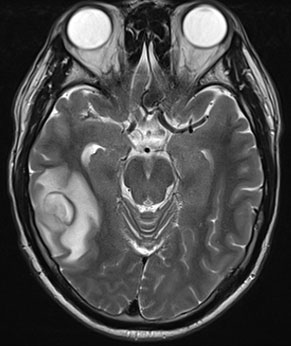

Un homme âgé de 33 ans, droitier, traité pour un diabète de type 1 par insuline, fut pris en charge, en janvier 2013, à la suite d'une première crise comitiale généralisée d'emblée. L'examen clinique tout comme la biologie usuelle était sans points d'appel. Il n'existait notamment pas de syndrome inflammatoire biologique.

L’IRM révéla l’existence d’une lésion fronto-temporale droite. La lésion apparaissait hétérogène avec un centre hypo-intense en T1 et hyper-intense T2 et Flair, entouré d'une zone en couronne en très discret hypersignal T1 et